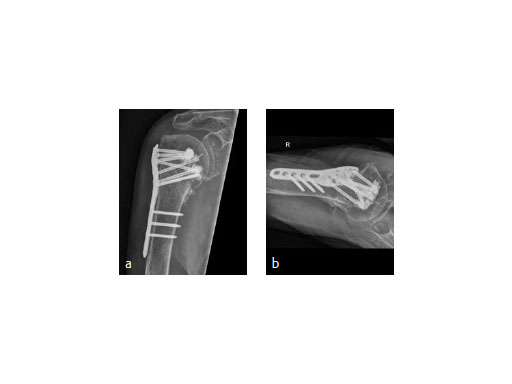

A 91-year-old female patient with osteoporosis had a dislocated 3-part proximalhumeral fracture in her right dominant arm (Fig 8).

The fracture was treated with PHILOS augmentation and healed in anatomical position (Fig 9).

(Case 2 provided by Franz Kralinger, Innsbruck, Austria)